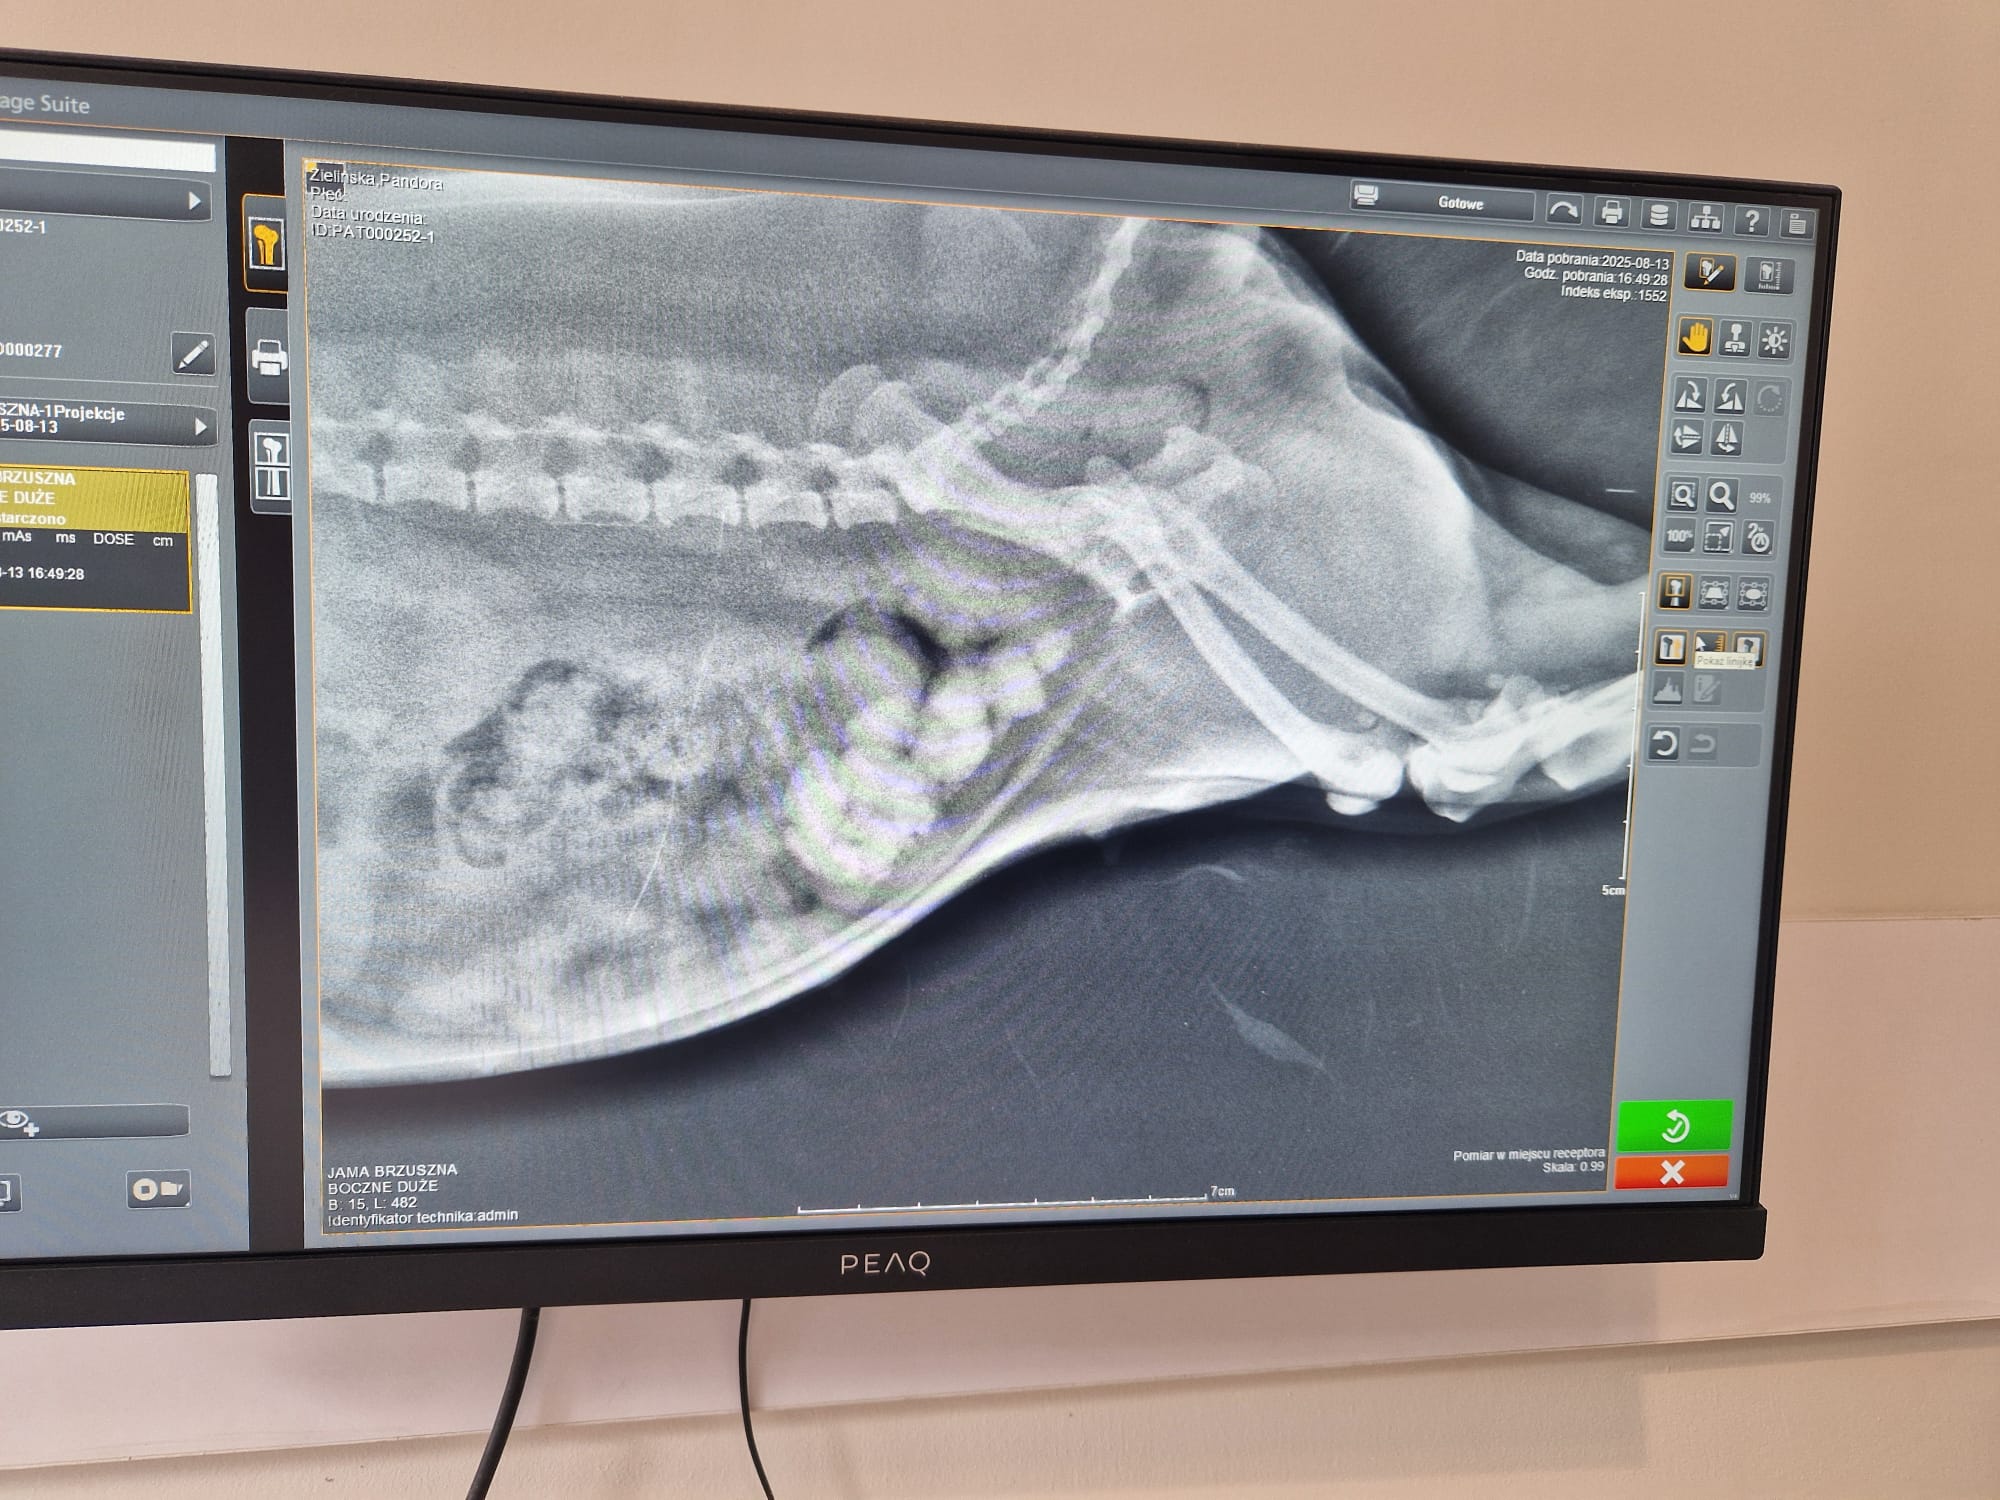

Śliczna Pandorka ma dopiero 3 lata a już przeszła sanację zębów z czego 6 straciła bo miała zapalenie dziąseł. W pełnym znieczuleniu 1500 zł trzeba było zapłacić. A tydzień temu się okazało że ma zapalenie pęcherza ale po bardziej szczegółowych badaniah z krwi potem USG ostatecznie RTG się okazało że ma w sobie pełno kamieni, co widac na zdjęciu. Nie mam pojęcia skąd u tak młodego psa tyle tego się zebrało w pęcherzu. Same badania wyniosły ok 900 zł. Obecnie psina ma krwiomocz jest na lekach przeciwbólowych oraz antybiotyku. Na cito zabieg potrzebny umówiony termin na środe 20.08.25 ale koszt to 2500 zł za samą operacje bo nie da się już w tym stadium kamieni rozpuścić. Proszę o pomoc dla tej słodkiej puchatej kuleczki aby mogła jeszcze sobie pobiegać i być nadal taka wesoła jaka jest pomimo tak strasznego bólu, który obecnie dzielnie znosi.